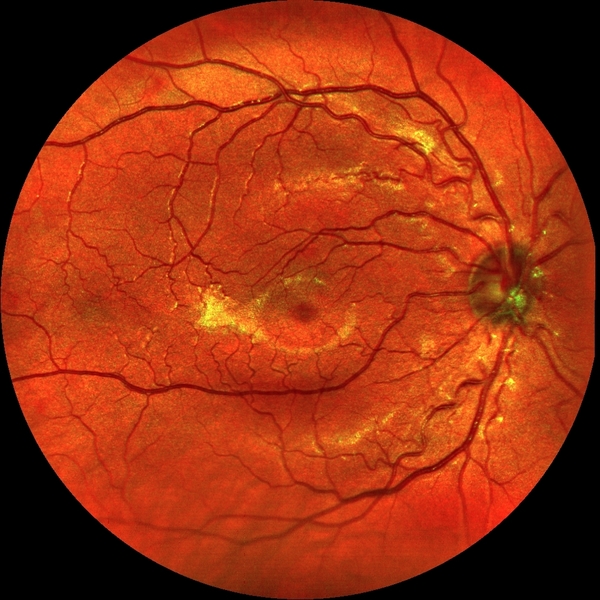

Screening: EasyScan (Netzhautuntersuchung, Augeninnendruckmessung etc.)

60 分钟

Ich möchte eine neue Netzhautuntersuchung mittels EasyScan machen lassen, evtl. auch in Kombination mit einer Augeninnnendruckmessung und einer Untersuchung des vorderen Augenabschnitts oder sonstige Untersuchungen.